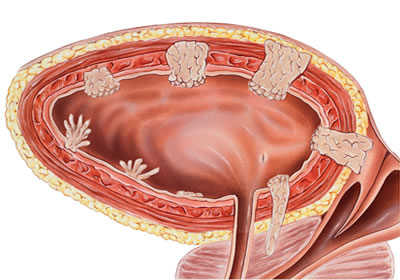

Mesane TUR ameliyatı kaç kere yapılır? Mesane tümörlerinin tanı ve tedavisinde uygulanan TUR-M (Transüretral Rezeksiyon) ameliyatı, bazı hastalarda tek seferde yeterli olurken, bazılarında birden fazla kez tekrarlanabilir. Tekrar gereksinimi; tümörün

Re TUR Ameliyatı (ikinci kazıma ameliyatı, yeniden ikinci kez yapılan TUM ameliyatı), mesane kanseri tanısı konulan hastalarda ilk TUR-M (idrar kanalından girilerek yapılan kapalı mesane kanseri ameliyatı) ameliyatından sonra uygulanan,

Mesane kazıma ameliyatı, TUR-M (TUR mesane) ameliyatı, kapalı mesane tümörü ameliyatı olarak da bilinir. TUR-M ameliyatı idrar kanalından kamera ile girilerek mesanedeki tümörlerin çıkarılması işlemidir. Üretra yani idrar kanalından girilerek